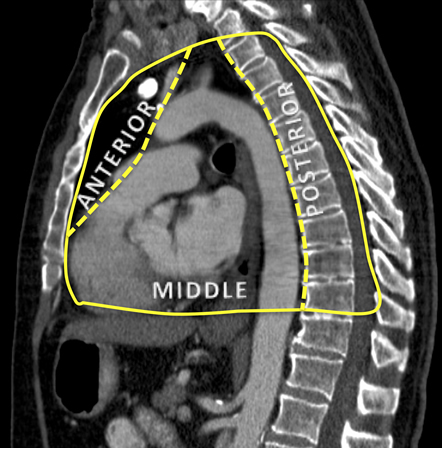

Compartimentos anatômicos do mediastino.

Do acervo de Dr. Muniappan